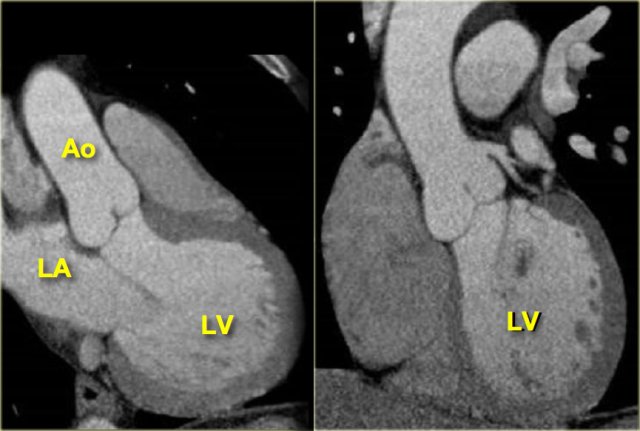

3-chamber view

When the border between the mitral and aortic valves is localized on the axial slices and the images are rotated from this point, a 3-chamber view like the image on the left can be reconstructed.

On this image, the left atrium, left ventricle, mitral-, aortic valve and proximal aorta ascendens are visible.